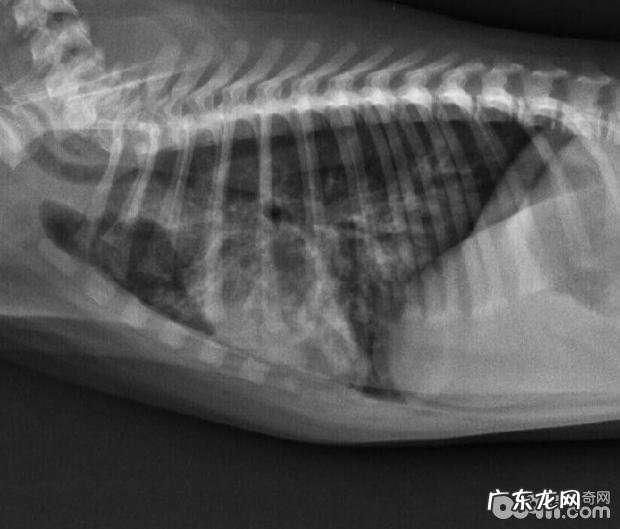

休重:9 。2kg,人体体温:40 。3℃,心跳:130/min,吸气:55/min,身型身体瘦 。精神面貌还行,鼻尖干躁,鼻腔有浓鼻涕,诱咳呈阳性,CDV(+),X光查验肺纹理增大增粗(如图所示),粪检(一切正常),血常规检查及电解质溶液基本参数见下表

X-光影象显示信息肺炎